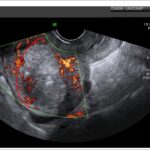

E quando falamos sobre a relação de corte com medula, estamos querendo dizer que a medida do córtex é diferente da medida da medula, ou seja, não segue a proporção regular estabelecida. Isso pode ser observado quando há uma linha amarela delimitando onde começa uma região e onde termina a outra, como nessa imagem aqui.

Agora, vamos falar sobre a imagem de pele e foice. A literatura define essa imagem como um processo inflamatório, uma fásia oca cuja origem pode ser ascendente (da bexiga), proteínas ou mesmo com uma lesão renal (por exemplo, nefrite tubulointersticial). A imagem de ultrassonografia vai depender da fase da doença. Em estágios iniciais, o rim pode parecer completamente normal. Em estágios mais avançados, é possível observar o aumento do tamanho do rim, o aumento difuso da ecogenicidade e a perda da definição corticomedular, como na imagem mostrada anteriormente.

Nos casos crônicos de pielonefrite, é possível observar a dilatação dos cálices e o sinal da medula. O sinal da medula corresponde ao aumento da ecogenicidade e ao destacamento da região de junção corticomedular, formando uma linha hiperecogênica na região medular paralela a essa junção. Esse sinal indica algum grau de injúria nos túbulos renais, principalmente na porção mais profunda da medula.